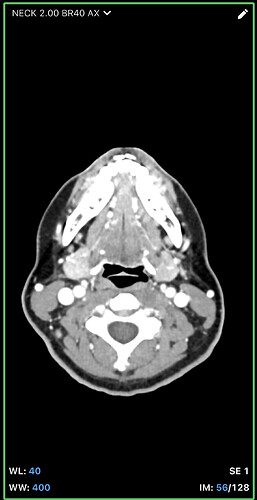

I think the best CT imaging view to look at whether your hyoid is digging into anything is by going into the axial view of your imaging. In the axial view look for the horseshoe shaped hyoid bone. I’ve attached what to look for. Take a couple screen shots and upload them and I can help interpret the imaging.

@leo this is the closest one. Can you go back to your axial view and go to the very last slice that you can see the tips? I think you might be one or two frames off. I attached my imaging to help. Our hyoids might be at slightly different angles so it might not be a perfect comparison, but I think you can go up a slice or two to see the tips better. Basically follow the bone until it disappears then go back one frame to capture it.

Hi, I’m so sorry for the delay in replying to you, we had some family stuff come up and this got pushed to the back burner for awhile. I’ve gone back a few frames, am I getting closer? I can also send you the whole CT if that would make things easier. I’m sorry, I’m not good with technology. I appreciate you taking the time to respond! Since we last spoke, I’ve developed a lot of neurological symptoms and weird physical ones like dizziness, headaches, brain fog, weird throbbing in my neck and head, can this all be tied in with hyoid bone problems? Thank you so much for your time!

@leo - The new symptoms you’ve just mentioned i.e. dizziness, headaches, brain fog, weird throbbing in my neck and head are all those we see associated with internal jugular vein compression. From what I can see in the images you posted, it looks like you may have that going on, but I’ll let @TML give you more information.